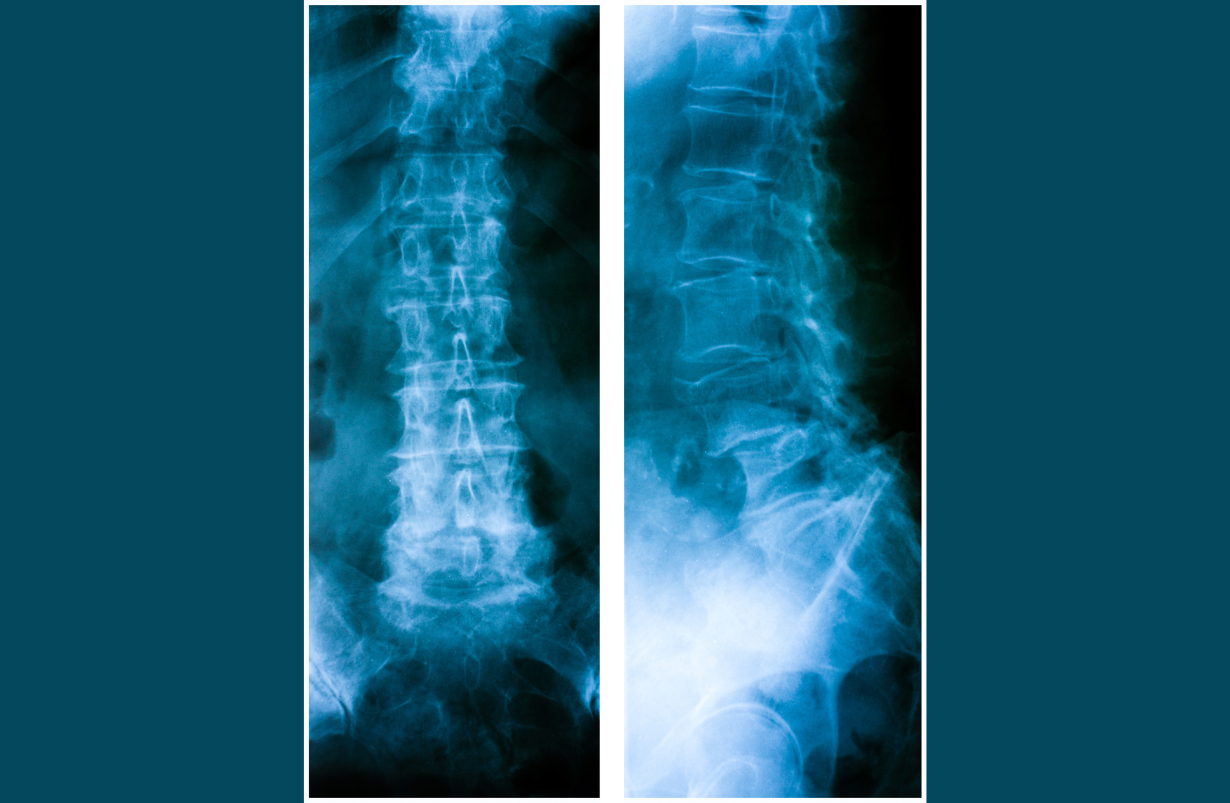

DEFINITION: Lateral curvature of the spine beyond 10 degrees. BENEFICIAL POSES: Vasisthasana, Elevated feet Vasisthasana, Ardha Chandrasana with belt. EXPLANATION: Lumbar scoliosis may be corrected by strengthening the muscles on the convex side of the lumbar curve with Vasisthasana. If there is also a thoracic curve, then Vasisthasana with feet elevated on a chair and/or Ardha Chandrasana must be used as well, again with the convex (thoracic) side down.The poses should be held for as long as possible and done at least one time every day (convex side downward). It is often quite difficult to determine the size and even the shape of scoliotic curves without an X-ray. Also pictured is whatthe spine looks like after Harrington Rod surgury. REFERENCE: Fishman, LM, Sherman KJ, Groessl EJ ”Serial Case Reporting Yoga for Idiopathic and Degenerative Scoliosis.” –. Global Adv Health Med. 2014;3(5):16-21. Fishman LM, Groessl EJ, Bernstein P. Two Isometric Yoga Poses Reduce the Curves in Degenerative and Adolescent Idiopathic Scoliosis. Topics in Geriatric Rehabilitation. 33(4):231-237, October/December 2017.

Spondylolisthesis

Spondylolisthesis occurs when one vertebra slides forward, backward or to the side, relative to the one directly below it. This slippage can occur in the cervical, thoracic (much less commonly) or the lumbar spine, and is generally forward slippage, anterolisthesis. Retrolisthesis is backward slippage of the vertebra above, and lateral listhesis involves slippage to one side or the other. Regardless of the direction, spondylolisthesis is graded in one way: Grade I: 0 - 24.9% of the lower vertebra is uncovered, Grade II: 25 - 49.9%, Grade III 50 -74.9%, and Grade IV: 75% or more. Anterolisthesis and retrolisthesis can cause all the neurological symptoms of a herniated disc or spinal stenosis, because it can narrow the spinal canal nd also shrink the opening through which the nerve root leaves the spinal cord (neuroforamen). .Generally Grade I is painless, though there are exceptions when e.g., the facet joints are swollen from arthritis, or there is a bulging or herniated disc narrowing the opening in the spine through which nerve roots exits (neuroforamina). However even Grade I, and certainly higher grades can leave the intervertebral disc uncovered by the vertebra above, and this can lead to paraesthesias, numbness, pain and weakness, and even bowel or bladder symptoms in extreme cases. Most cases are traumatic in origin, but some authorities assert that it can be congenital, particularly when the bone connecting the facets to the vertebral body (the pars interarticularis) is fractured. Yoga is particularly useful in the most common type of spondylolisthesis, anterolistghesis. In general with anterolisthesis, the strategy is to move back the forward-slid vertebra. Abdominal strengthening and forward bending, making the spine as long as possible, are the poses that do this. Retrolisthesis is treated just the opposite way: strengthening the quadratus lumborum muscles, and doing back extension poses. Lateral listhesis is rarely symptomatic, although it makes the yogic treatment of scoliosis more difficult. See 'scoliosis' for details.